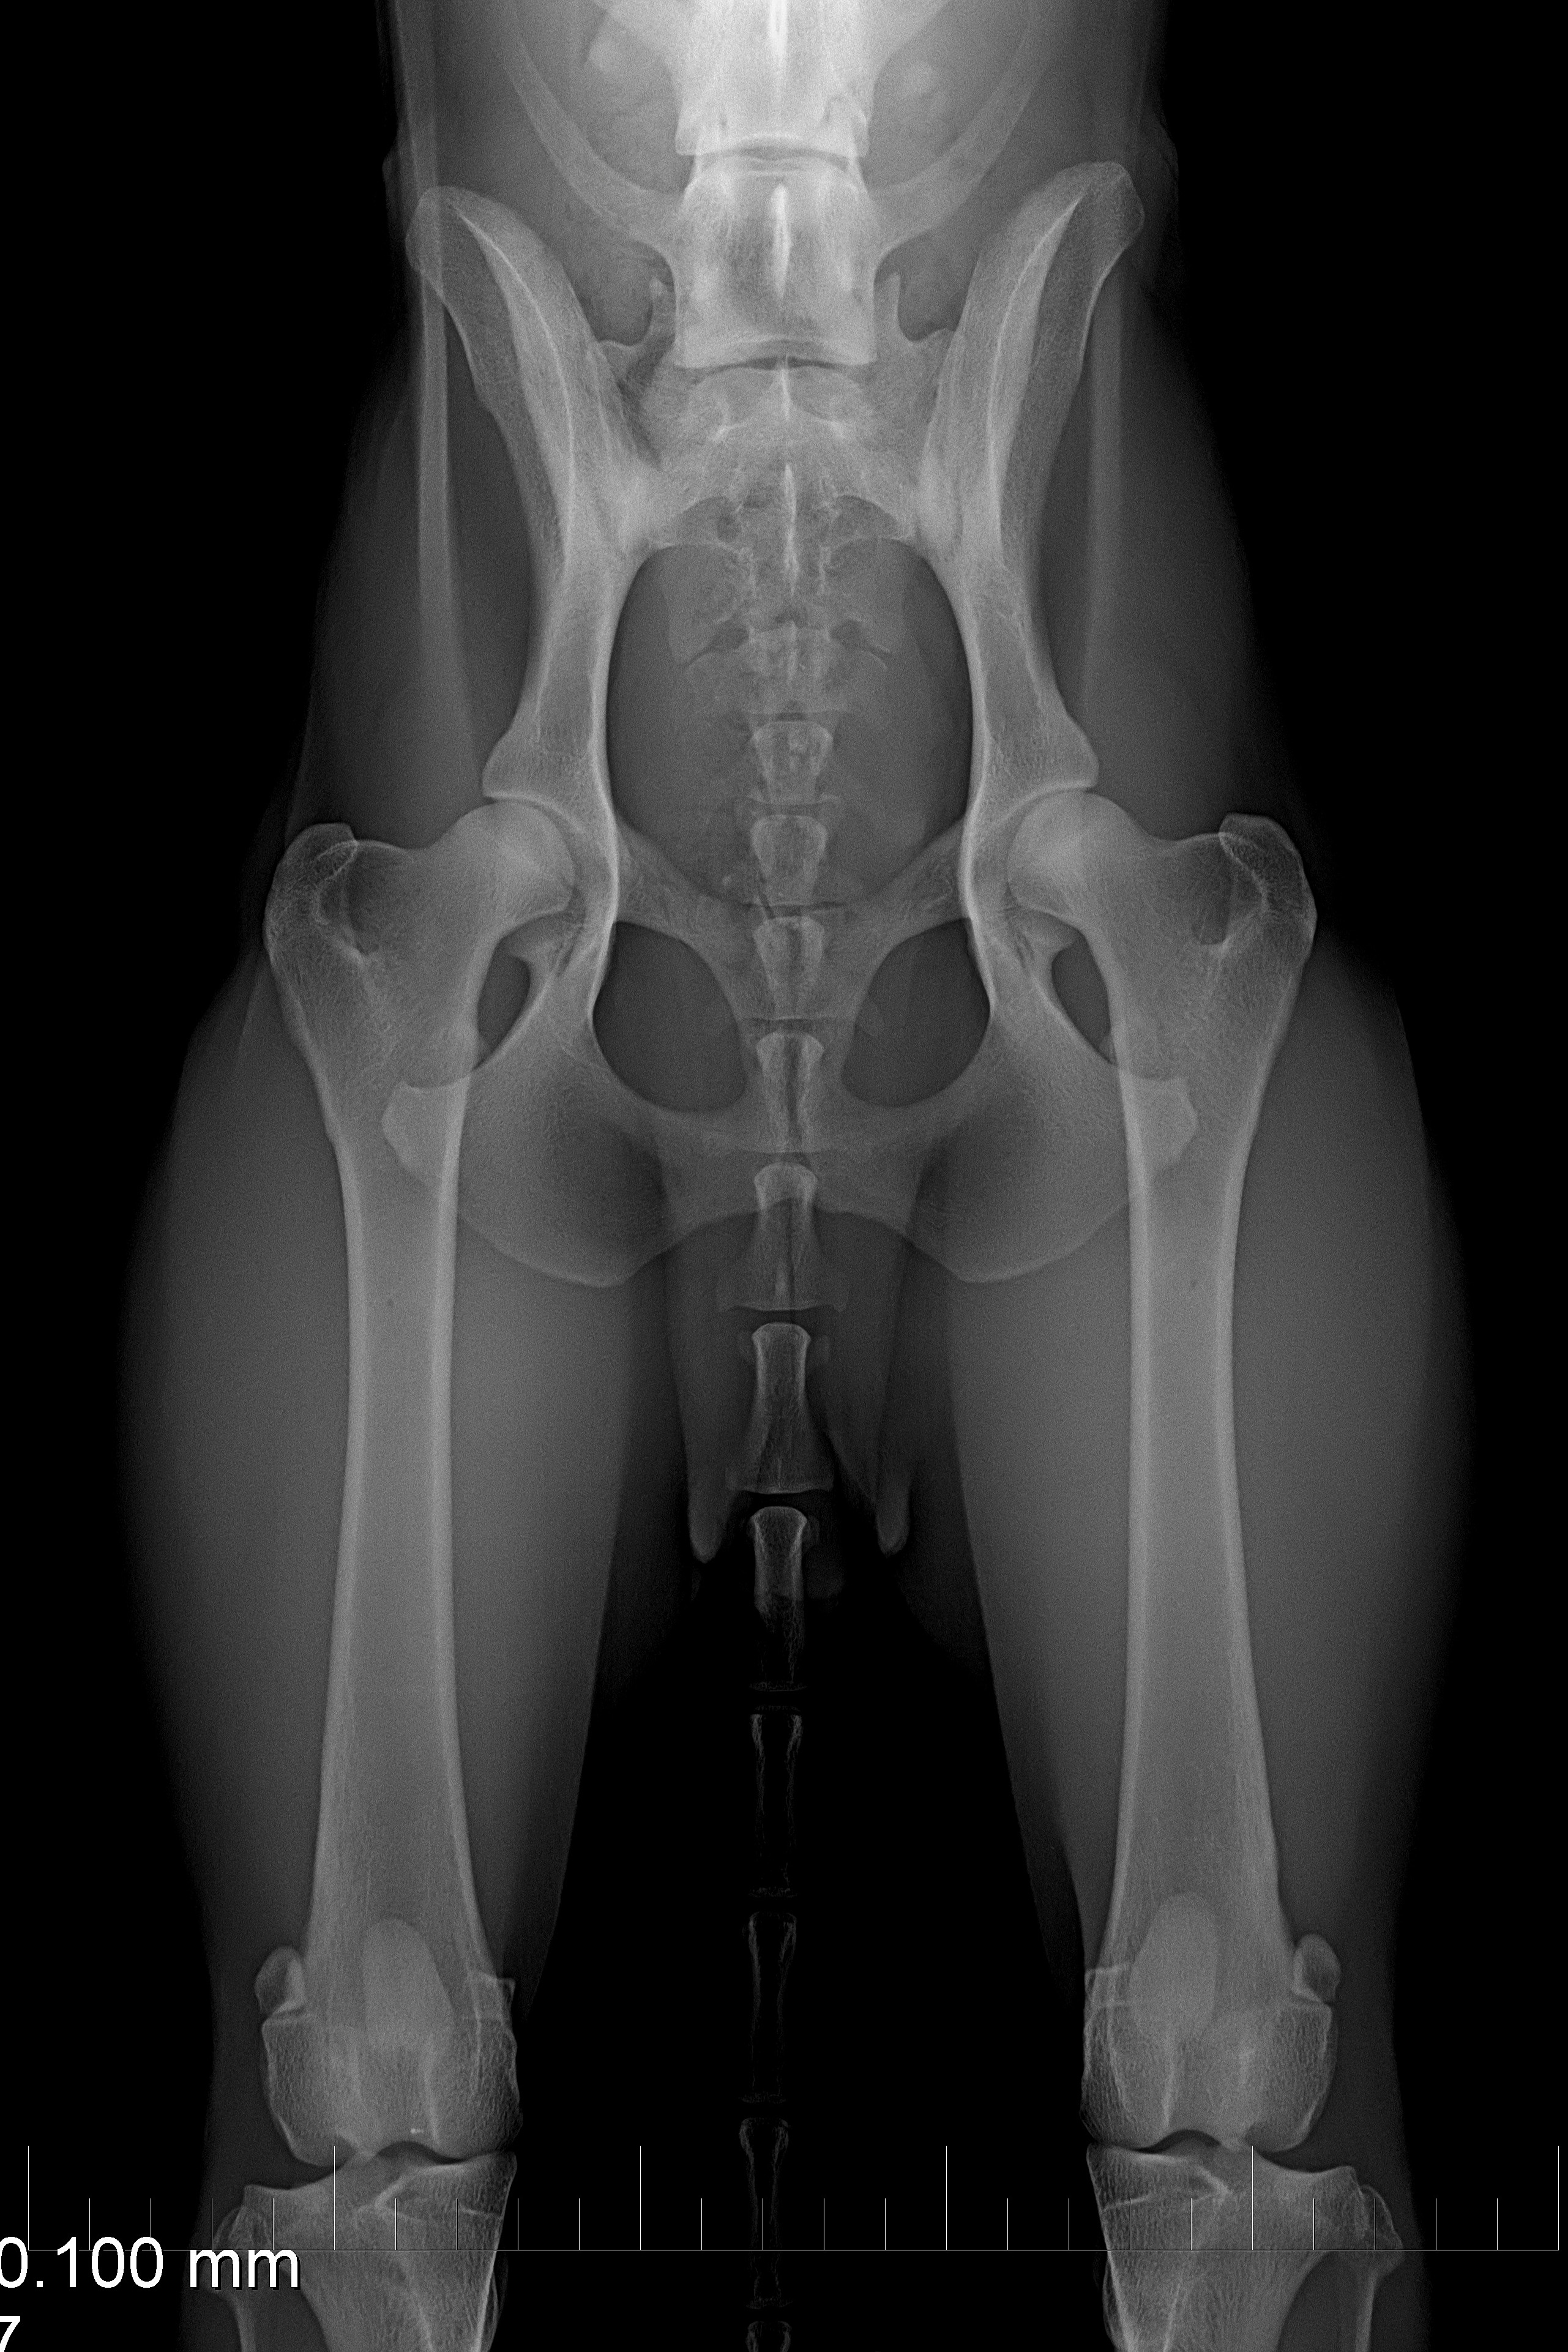

(4) 7 měsíců VD 2

(4) typ 3 po korekci polohy pánve 2